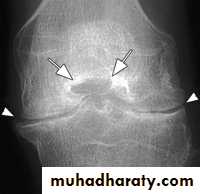

Osteoarthritis :

OA is the commonest form of arthritis , resulting from wear & teat of the articular cartilage .Features seen in OA :

1.joint space narrowing. 2. Osteophytes. 3. Subchondral sclerosis . 4. Subchondral cysts.

OA

1.joint space narrowing maximal at weight- bearing site.

2. erosions don’t occur but crumbling of the joint surface may mimic erosions.

3.subchindral cyst & sclerosis may be seen.

4.sclerosis is a prominent feature.

5. no osteoporosis.